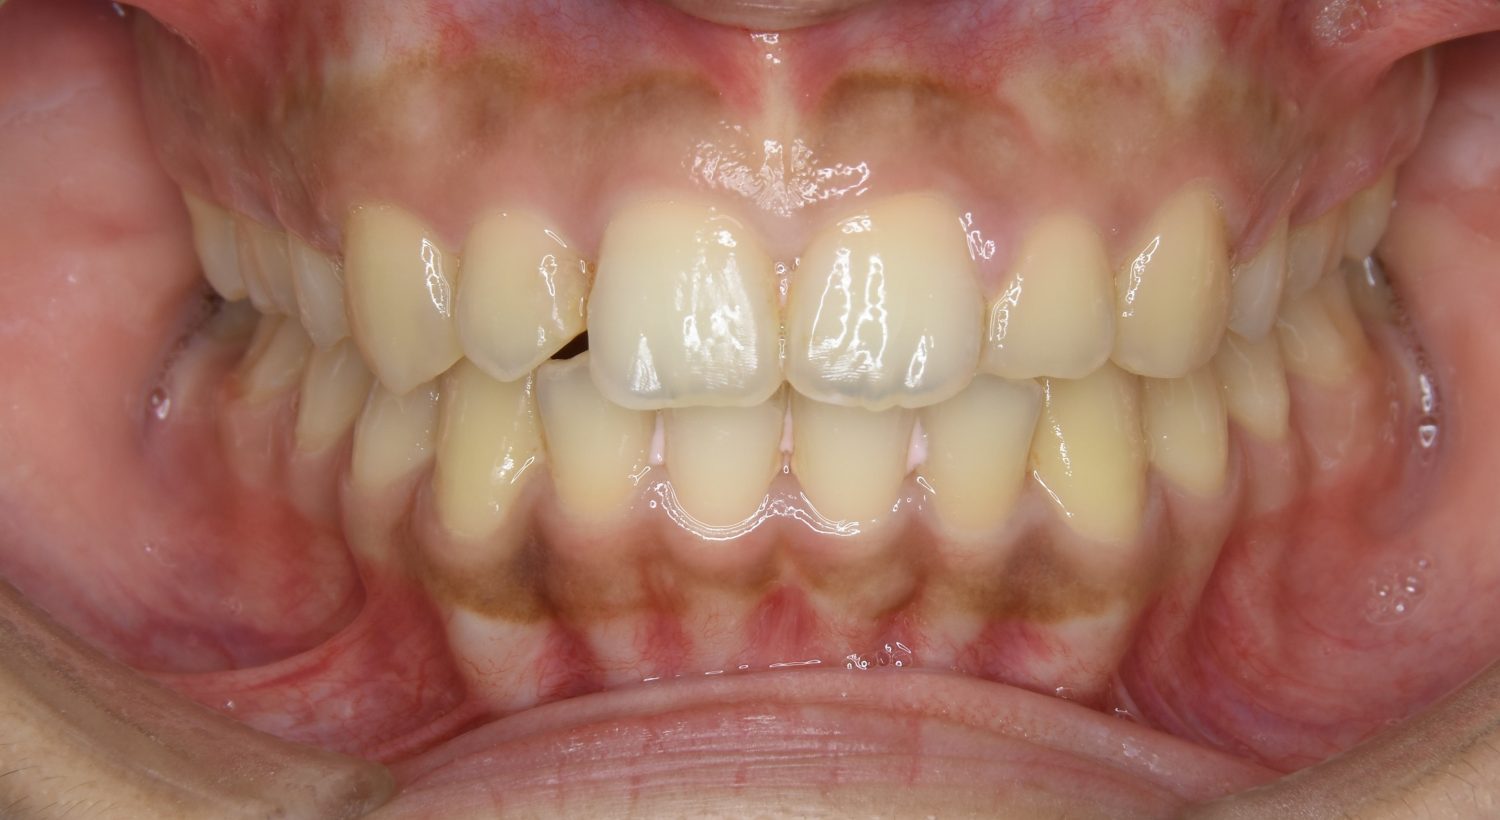

前歯部開咬の症例紹介②

Before

After

主訴

前歯で物が噛めない

治療内容

上下ラビアルブラケット(唇側装置)に矯正用アンカースクリューを併用し非抜歯で治療を行いました。

治療費

1,000,000 円(税込)

治療期間

26ヶ月

通院回数

27回

想定されたリスク

※歯根吸収、歯肉退縮、歯髄壊死、顎関節症状

丸山和宏先生

ピーススマイル矯正歯科

上下の前歯が開いており前歯では全く噛めていない状態でした。臼歯の圧下を行うことで機能面のみでなく審美面も改善しました。